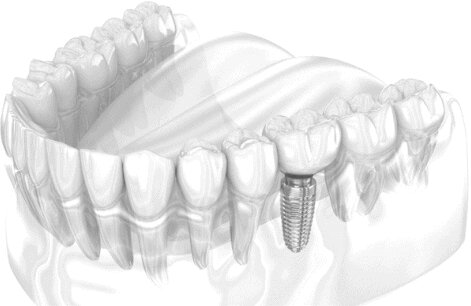

Aceasta procedura moderna pres ... | | | | | |  Implant dentar Implant dentar |  | Dent Park - Clinica stomatologica Bucuresti

Ce este implantul dentar - sol ... | | | | | |  Odontoterapie Odontoterapie |  | Dent Park - Clinica stomatologica Bucuresti

Consultatii Prima vizita: exa ... | | | | | |  Implanturi dentare Implanturi dentare |  | Opera Dental - Clinica stomatologica, Bucuresti

Parodontologie Endodo ... | | | | | |